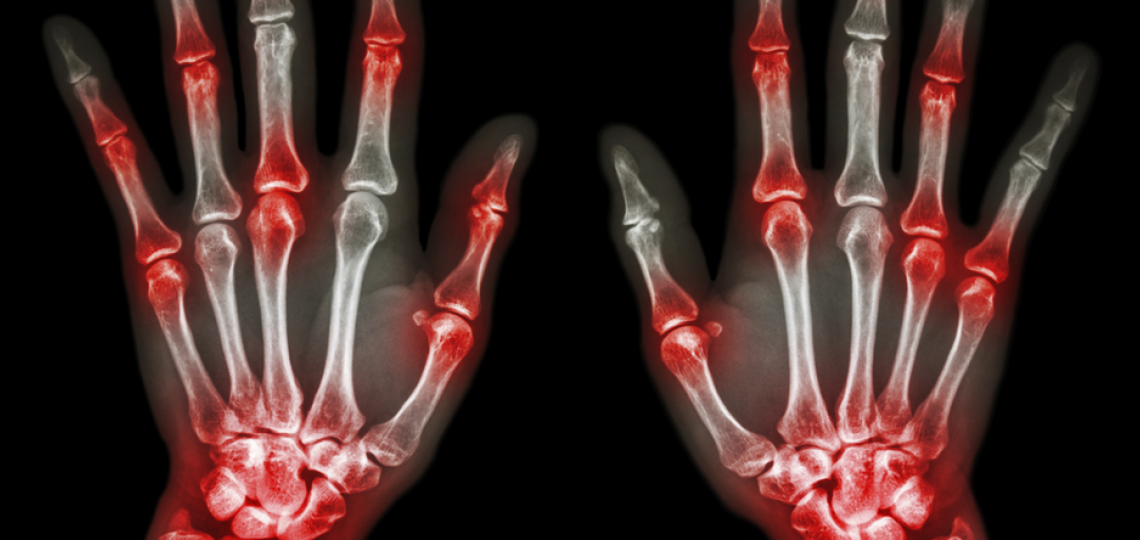

Expert Care for Rheumatic Disorders

Baylor Medicine Rheumatology Clinic at Baylor St. Luke’s Medical Center McNair Campus treats and manages rheumatic diseases that affect the joints, muscles, bones, skin, and internal organs in adult patients and patients with rheumatologic issues diagnosed in childhood as they transition to young adults.

Rheumatology encompasses a variety of complex and multi-system conditions that are autoimmune or inflammatory in nature including:

- Inflammatory arthritis

- Rheumatoid Arthritis